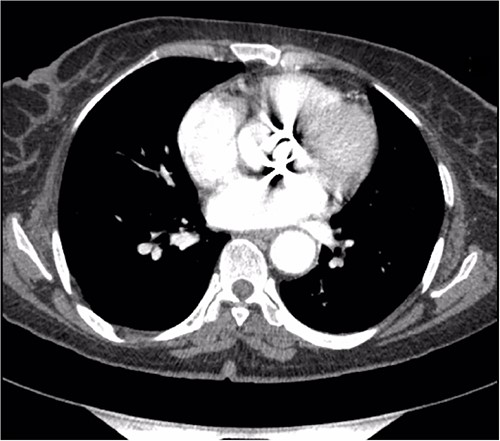

Preoperative CT demonstrating a previous aortic mechanical valve prosthesis.